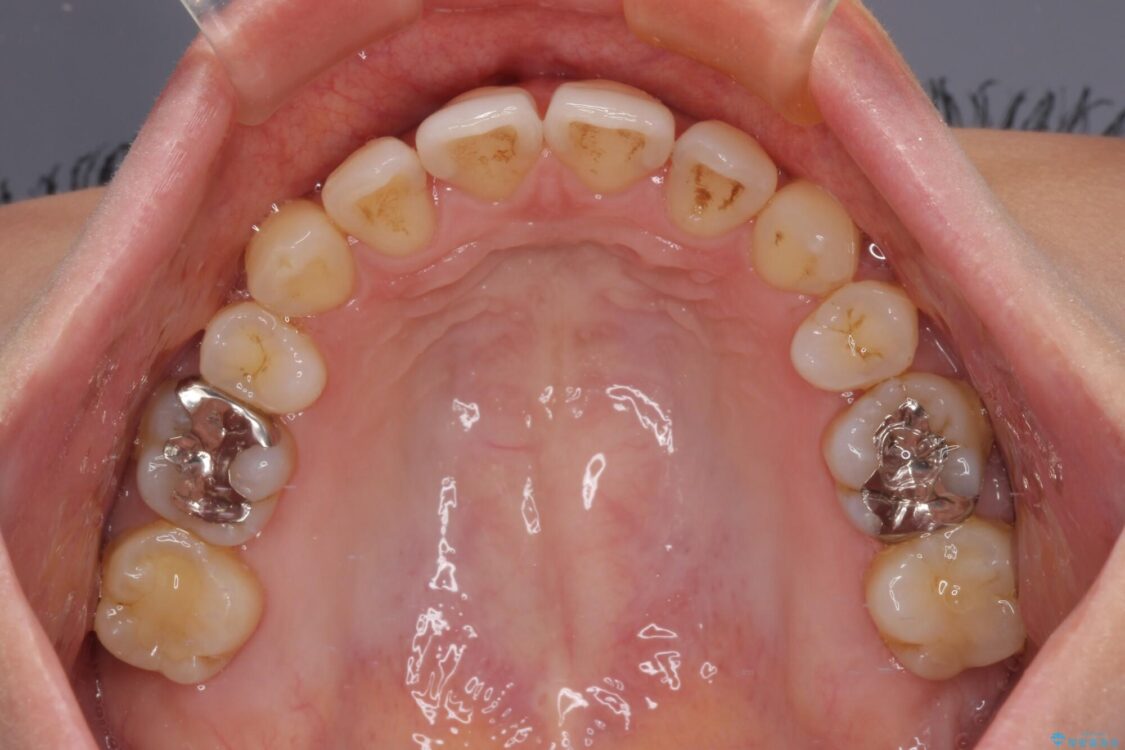

治療前

• 上顎前歯の突出を軽減 インビザラインによる抜歯矯正 治療前画像